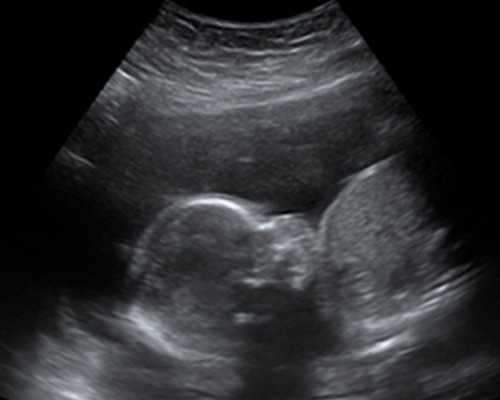

带娃游泳确实是蛮酷的一件事,对宝宝来说,可以帮助刺激ta的视觉、温觉、嗅觉、触觉以及平衡觉;可以促进关节、肌肉、神经的良好发育;还有模拟母体中的羊水环境,消除宝宝的焦虑感。